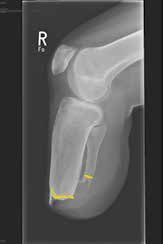

Nerven

Bei Revisionen ist auffallend, dass Nerven zum Teil bis in den Stumpfendbereich liegengelassen worden sind (siehe Abb. 8). Man sollte sich auf die Nn. fibulares, den N. tibialis und den N. suralis konzentrieren.

Alle Nerven werden um etwa 5 cm, wenn möglich mehr, gekürzt und in die Weichteile verlegt, so dass entstehende Neurome mehr oder weniger geschützt liegen. Bei der Absetzung erfolgt eine Unterbindung des Nervs mit begleitendem Gefäß, wenn es sich um einen nicht durchblutungsgestörten Stumpf handelt.